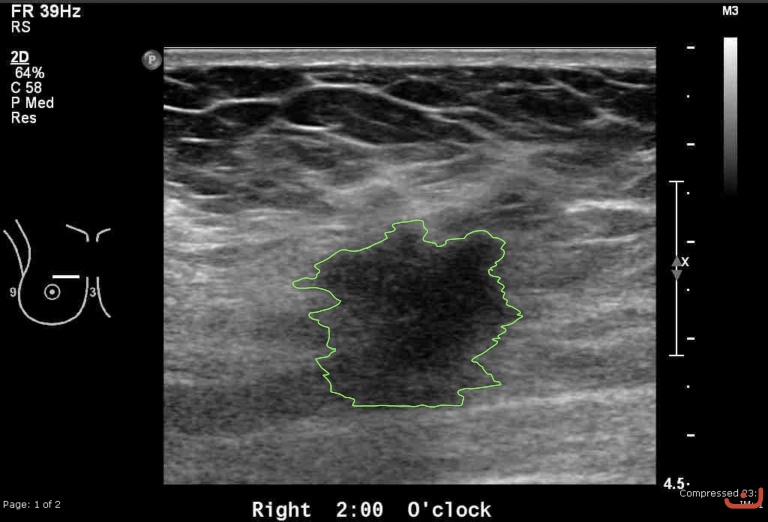

Malignant solid mass

Friday, 22 May 2015

180.06 KB (768 x 522 px)